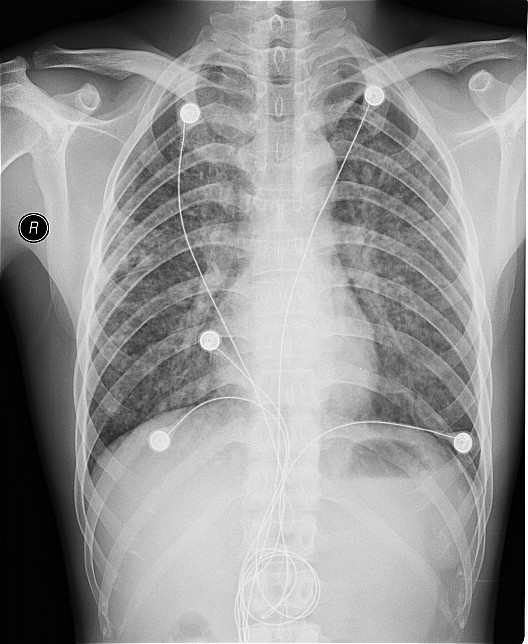

一钨矿工厂因有毒气体泄漏(据说是硝酸)造成十多名工人中毒,均出现不同程度的咳嗽,气逼,心跳加快等中毒症状.其中有几例患者胸片出现小点片状,结节状阴影.是此次中毒引起的肺部改变还是原来就患有矽肺病或其它病变.

肺水肿,及原来就患有矽肺病

原就有的矽肺,未见中毒性肺水肿

支持矽肺,未见肺水肿.建议治疗后复查

矽肺,部分胸片可见肺水肿。治疗复查